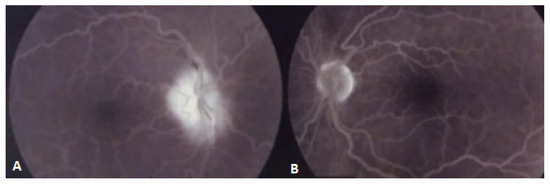

Non-Simultaneous Bilateral Ischemic Optic Neuropathy Related to High Altitude and Airplane Flight in a Patient with Cerebral Small Vessel Disease

2. Case Report